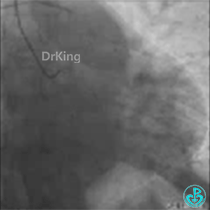

正如预测的一样,分支导丝始终无法通过分支开口,采用双腔微导管辅助翻转导丝技术顺利进入。

从球囊扩张不充分可以看出病变重,病变较硬且成角严重,计划使用切割球囊处理。

用2.5×10mm球囊以10atm×10s扩张。